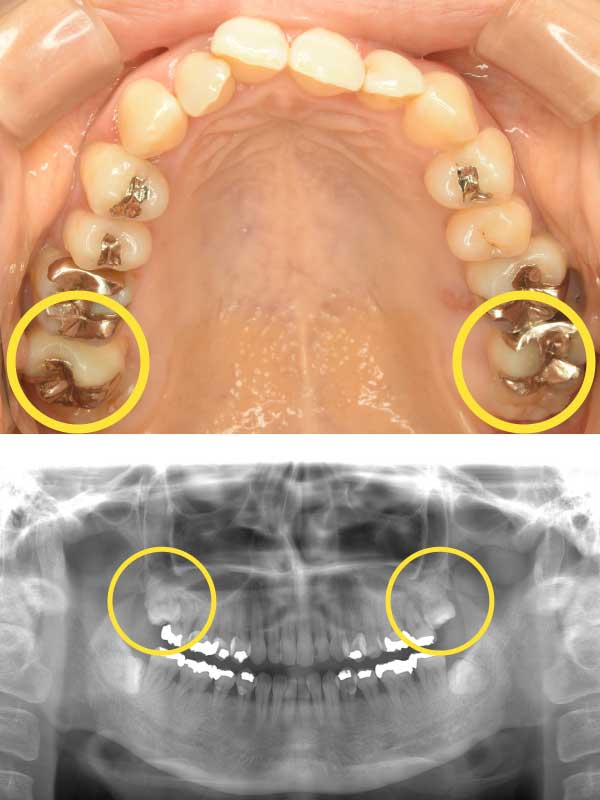

| 主訴 | 奥歯をどうにかして残したい。 他院で抜歯と言われ、インプラントが必要と診断されたが、諦めきれない。 |

|---|---|

| 治療内容 | 親知らずを活用した矯正治療 |

当院では、抜かずに残しておいた親知らずを「矯正」で移動させ、奥歯として蘇らせます。

他院で「抜歯してインプラント」と言われた欠損部位に対し、当院が提案するのは、親知らずを矯正装置でゆっくりと手前に引き寄せ、空いたスペースを埋める治療法です。

本来は抜歯対象になりやすい親知らずを「天然のインプラント」として活用する、非常に身体に優しいアプローチです。